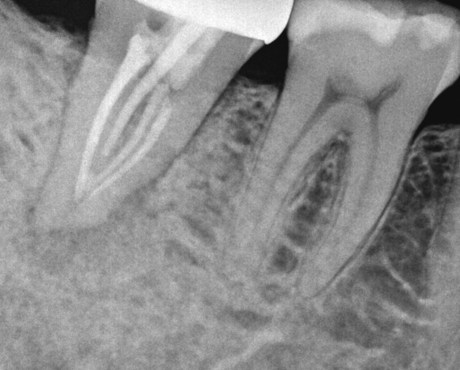

치료 전

치료 직후